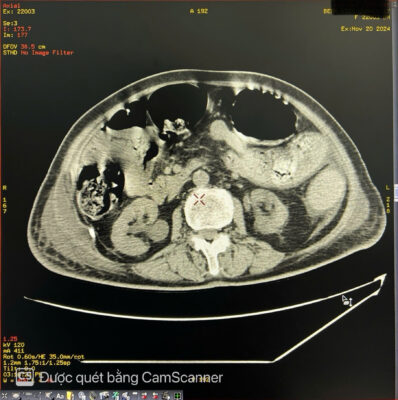

🚑 Một phụ nữ 84 tuổi đến khám với tình trạng đau bụng kèm táo bón mãn tính lâu ngày. Khi khám, bụng căng to, nhiều hơn ở bên trái. Sờ thấy một khối u mơ hồ ở hố chậu trái. Chụp X-quang bụng không chuẩn bị cho thấy giãn đại tràng lên và đại tràng ngang, toàn bộ đại tràng xuống chứa đầy phân. Các quai ruột non bị di lệch sang bên phải bụng. Siêu âm bụng thấy bụng căng nhiều hơi. Chụp cắt lớp vi tính (CT) ổ bụng cho thấy đại tràng xuống và đại tràng sigma giãn lớn chứa đầy phân kèm vôi hóa không đều tạo thành một khối u phân trong lòng đại tràng, có kích thước # 8 x9 x 26cm. Đại tràng lên và đại tràng ngang giãn d# 6.4 cm. Hai thận ứ nước độ I. Thành đại tràng dày nhẹ, còn cấu trúc lớp, thâm nhiễm mỡ nhẹ xung quanh, kèm ít dịch hạ vị. Không thấy khối u hoặc hẹp lòng ruột cản trở ở vùng trực tràng-sigma. Bệnh nhân được điều trị bảo tồn bằng thụt tháo và thuốc nhuận tràng. Hiện tại bệnh nhân ổn định, các triệu chứng cải thiện rõ rệt.

Hình ảnh 1 Hình ảnh 2

Hình ảnh 3 Hình ảnh 4 Hình ảnh 5